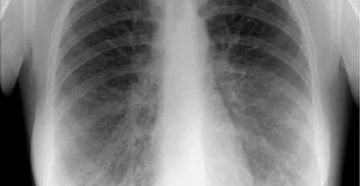

Диагностика заболеваний легких и дыхательных путей Заболевания дыхательных путей доставляют дискомфорт не только самому больному,…